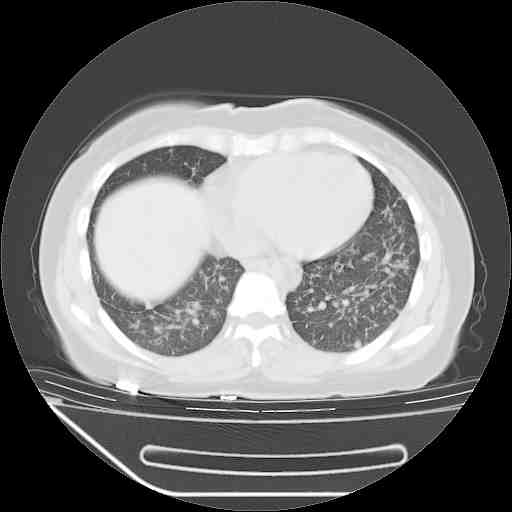

f50,肺ca治疗后,做过穿刺,确诊是肺ca,大家看看这是去年12月做的

考虑  腺癌肺内转移,治疗较前病灶缩小、减少

支持肺癌并肺内淋巴管转移,

肺癌并肺内转移,这种疾病治疗后在影像上看略有好转,不是很显著,但是肿瘤治疗效果影像只是一方面。

支持肺癌并肺内淋巴管炎,  原发灶小了,但转移较前片明显了.

支气管血管束粗而乱,考虑肺癌肺内淋巴管转移,右侧乳房第一二层软组织成份较左侧多,不会有问题吧?

支持右肺下叶周围型肺癌并肺内淋巴管炎,  原发灶小了,但转移较前片明显了.。

标准的细支气管肺泡癌呀!治疗后病情有所控制,也没治愈的迹象!